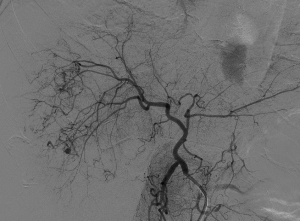

入院后,為患者給予補液,在局部麻醉下行DSA引導下經導管肝腫瘤動脈栓塞術。

肝癌破裂大出血并失血性休克患者往往病情急、危、重,如果治療不及時可能短期內死亡。未開展介入治療的醫院對此類患者只能給予輸血,補液,急診手術,在插管全麻下行開腹手術治療。但開腹手術往往切口長、手術時間長、手術創傷大,麻醉副作用大。可能術后出現肝功能衰竭,再出血,腹腔感染,切口疼痛,切口感染等并發癥。介入手術則往往較少出現這些并發癥。介入手術只需要在腹股溝穿刺一個2mm的小孔,置入導管到肝動脈,注入栓塞劑栓塞肝腫瘤的動脈,手術創傷小,止血可靠,除肝區疼痛及發熱外,較少出現其它并發癥,病人舒適度明顯提高,而且能早期進食及下地活動,恢復快,能縮短住院時間,具有療效好且微創的優點。